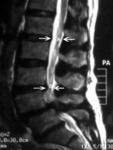

Magnetic resonance imaging of spinal stenosis: (A) demarcates the normal sagittal diameter of the spinal canal. (B) demarcates severe narrowing of the spinal canal

Courtesy of Dr K. Singh; used with permission

Magnetic resonance imaging of spinal stenosis: arrow points to the moderately stenotic spinal canal caused by hypertrophic facets and ligament flavum